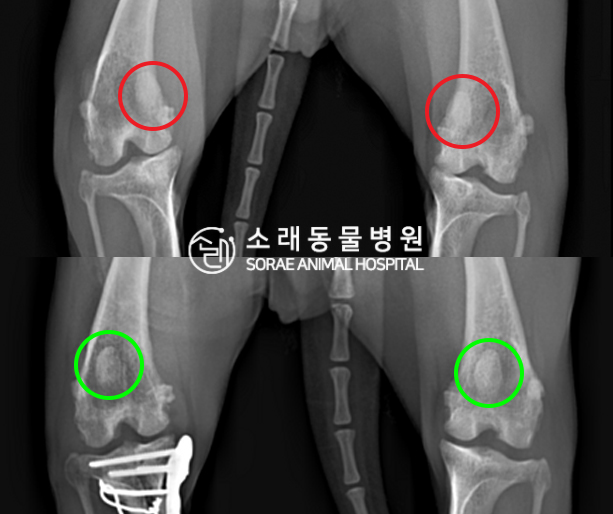

수술전과 수술후에 촬영한 이슬이의 슬개골

방사선 사진입니다. 나란히 놓고 비교해보니

슬개골의 위치에 확연한 차이가 있는 것을

확인해 볼 수 있는데요. 내측으로 탈구되어 있던

슬개골이 원래 제자리인 활차구에 예쁘게

자리 잡고 있는 모습을 확인할 수 있었습니다.